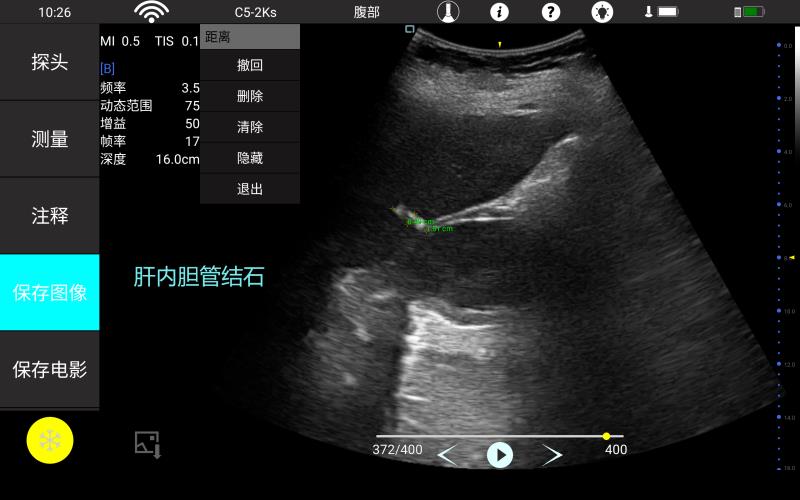

腹部

肾脏

妇科产科

心脏

肺等